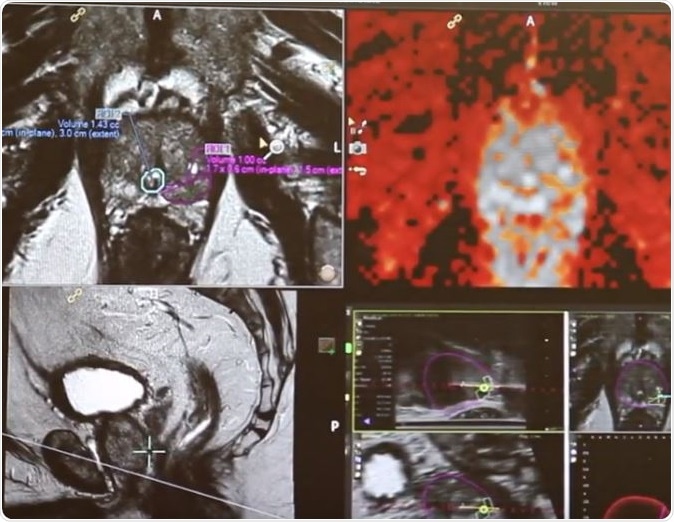

The team wrote that these “biocompatible gold nanoparticles”. Have a special ability to absorb the light at near-infrared wavelength and turn it into heat. This localized generation of the heat helps in killing the targeted tumour cells and ultimately reduced the tumour without affecting the healthy cells. The study showed that use of these nanoparticles helped prolong the remission of the cancer patients when used alongside “magnetic resonance–ultrasound fusion imaging” that was used to locally burn away the “low-intermediate-grade tumors within the prostate.”

For this study the team included 16 men (aged between 58 and 79 years) with diagnosis of “low- or intermediate-risk localized prostate cancer.” They were all given intravenous infusions of gold silica nanoparticles and “high-precision laser ablation”, along with “multiparametric MRI of the prostate at 48 to 72 hours.” For these patients ultrasound guided biopsies were taken from the tumours at 3 and 12 months after the therapy. Along with these targeted fusion biopsies, the patients also underwent 12 core systematic biopsy at 12 months after the therapy.